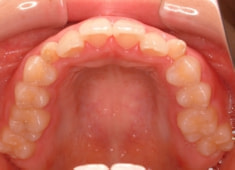

治療前